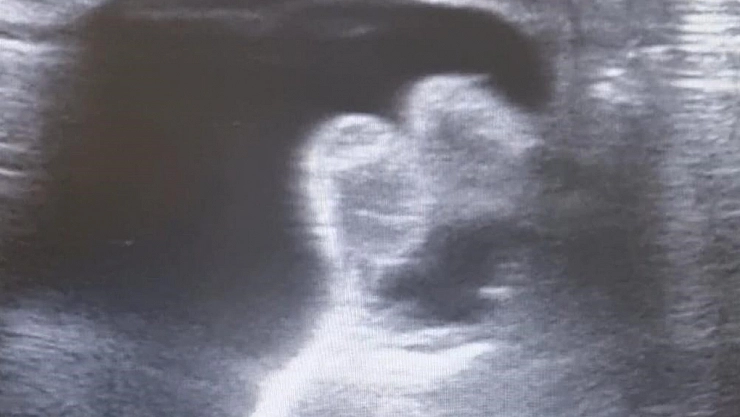

Edinilen bilgilere göre, kanlı ishal ve genel durum bozukluğu nedeniyle Hitit Üniversitesi Erol Olçok Eğitim ve Araştırma Hastanesi’ne kaldırılan 9 aylık bebeğe halk arasında "bağırsak düğümlenmesi’’ olarak bilinen invajinasyon tanısı konuldu. Yapılan değerlendirmeler neticesinde invajinasyonun düzeltilmesi için transrektal yoldan işlem yapılması kararı alındı. Radyoloji Kliniği Eğitim Görevlisi ve Çocuk Radyolojisi Uzmanı Doç. Dr. Altan Güneş ve Çocuk Cerrahisi Kliniği Eğitim Görevlisi Prof. Dr. Çağatay Evrim Afşarlar tarafından acil serviste bebeğin düğümlenen bağırsağı ameliyata ihtiyaç kalmadan tedavi edildi.

Konu hakkında bilgi veren Çocuk Radyolojisi Uzmanı Doç. Dr. Altan Güneş, “İnvajinasyon veya halk arasındaki adıyla barsak düğümlenmesi, çocuk hastalarda sık görülen, erken tanı ve tedavi gerektiren, genellikle kanlı ishal, karın ağrısı ve genel durum bozukluğu gibi şikayetlerle hastaneye başvuru sebebi olan, tedavi edilmediği takdirde barsak delinmesi, barsak kaybı ve ağır vakalarda ölüme kadar gidebilecek ciddi bir acil durumdur. Tedavisinde ameliyata alternatif seçeneklerden birisi olarak ultrasonografi eşliğinde redüksiyon seçkin merkezlerde uygulanan bir tedavi yöntemidir. Bu sayede hastaların hastanede kalış süresi azalmakta, hastalar cerrahi yöntemlerin olumsuz yan etkilerinden korunmakta ve hızla, bazen aynı gün iyileşebilmektedirler’’ dedi.